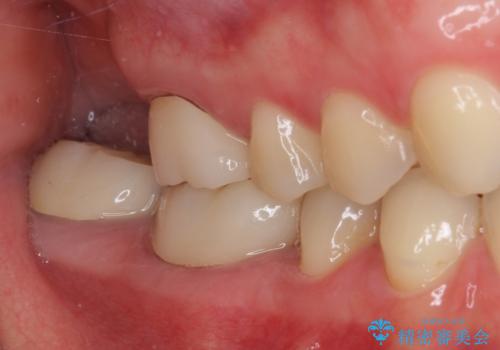

- 前歯の隙間と奥歯の目立つ銀歯を気にして来院された患者様です。

インビザラインにより下顎前歯の隙間を閉じるとともに、奥歯の咬み合わせを改善させることとしました。

矯正治療後には、銀歯のクラウンをセラミッククラウンへ替える補綴治療を行うこととしました。